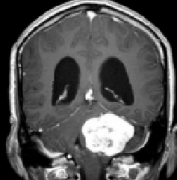

问:听神经瘤的主要临床表现有哪些?听神经瘤术后有后遗症吗? 答:听神经瘤是从内耳道到小脑桥角部发展的良性肿瘤,但很少是恶性的。大多数肿瘤起源于前庭雪旺氏细胞,因此恰...

问:听神经瘤治疗会有什么后遗症? 答: 听神经瘤 是一种良性肿瘤,从负责听觉和平衡神经发生。良性肿瘤不会扩散到身体的其他部位,但它们仍然可以长到足以压迫周围组织,需要...